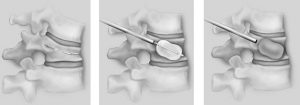

A new technique of percutaneous stabilization of vertebral fractures [Kyphoplasty], however, allows for restoration of the vertebral body height with injection of cement to stabilize VCFs. The patient is placed in a prone position. Using fluoroscopy, the surgeon introduces a cannula into the vertebral body through the pedicle posteriorly. A balloon is subsequently utilized to inflate and “jack up†the vertebrae to its normal, non compressed height. Subsequently, cement is injected into the void to prevent future collapse. [Figures 1 and 3].

Figure 2 and 3: With Kyphoplasty, a tube is introduced into the broken vertebrae which can be lifted back to its pre-fracture shape.